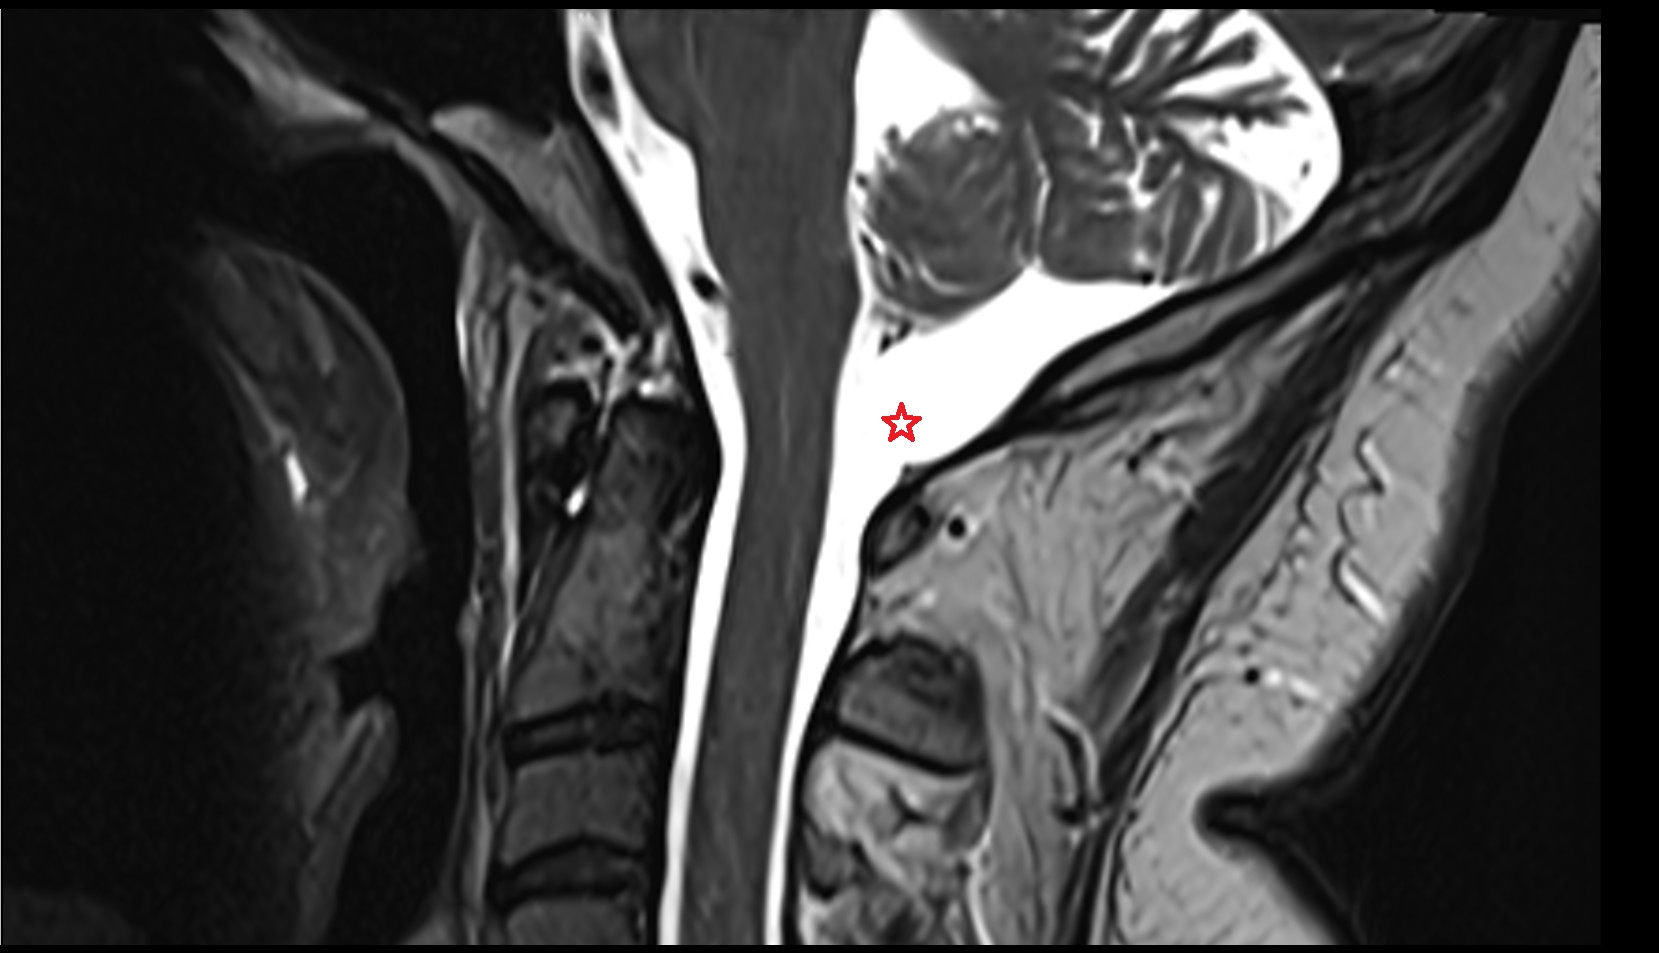

- Spinal cord

- Anterior longitudinal ligament

- Posterior longitudinal ligament

- subarachnoid space of spinal cord

- Cisterna magna